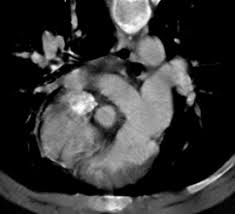

Supravalvular Aortic Stenosis Williams Syndrome Cardiac Case Studies Ctisus Ct Scanning

Computerized Tomography Use In Williams Beuren Syndrome Aortopathy Kalis Nn Sulaibikh Lk Al Amer Sr Al Amer Hy Heart Views

Contrast Enhanced Cardiac Computed Tomography Demonstrating Findings Of Download Scientific Diagram